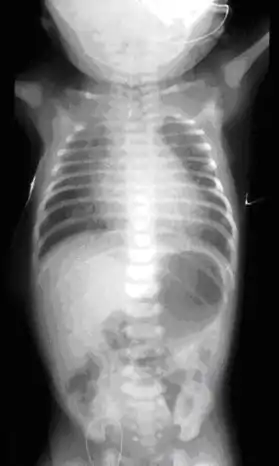

On plain X-ray, a feeding tube will not be seen pass through the esophagus and remain coiled in the upper oesophageal pouch.[8]

Plain X-ray of the chest and abdomen showing a feeding tube unable to move beyond an upper esophageal pouch.